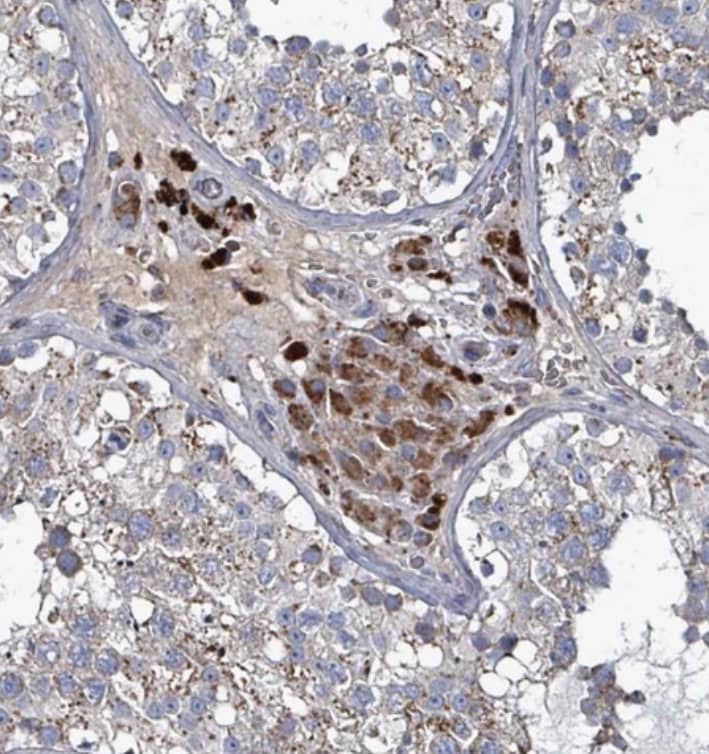

Immunohistochemistry-Paraffin: ABHD18 Antibody [NBP2-30555] - Staining of human kidney shows strong cytoplasmic positivity in cells in tubules.

Staining of human testis shows strong cytoplasmic positivity in Leydig cells.